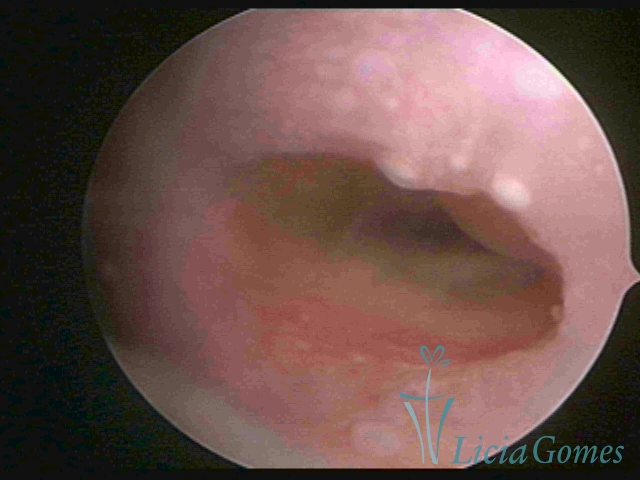

Primeira porção ou setor proximal ou setor inferior:

Durante a fase proliferativa, encontramos muco claro e cristalino pouco aderente à óptica. As criptas e as papilas apresentam-se um pouco edemaciadas e vascularizadas, micro vesicular, lembrando cachos de uva.